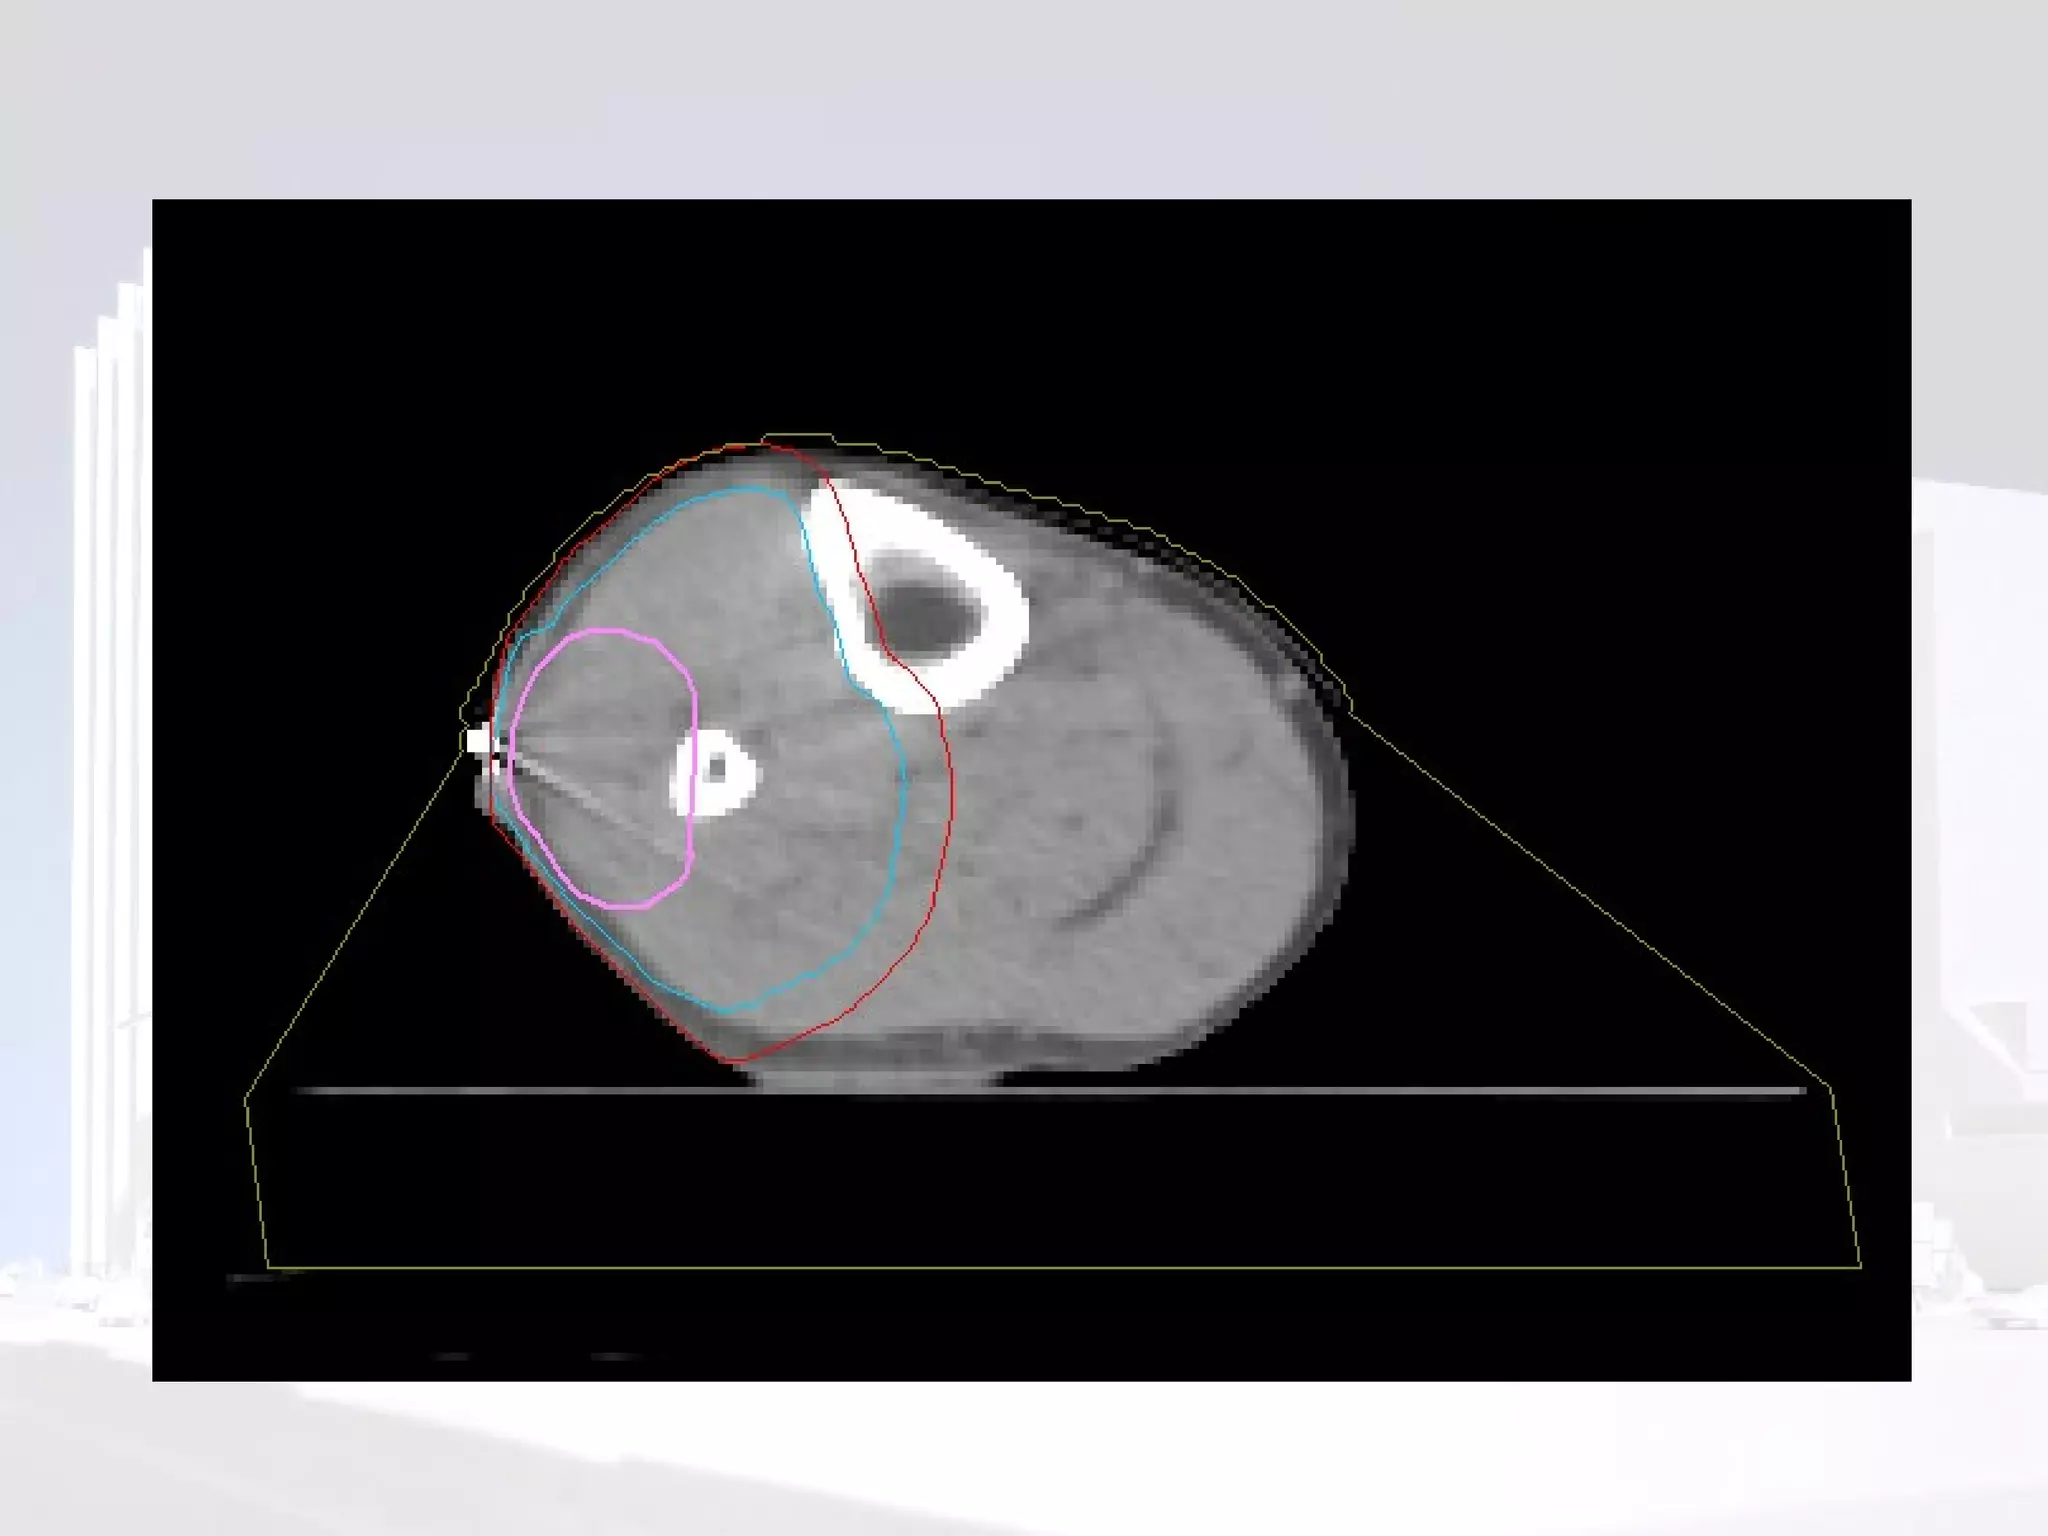

Planning

Phase I  Volume definition GTV  reconstructed from pre-op imaging. Consider compartment at risk of microscopic spread. Should include biopsy site and scar CTV  (length) =  GTV  + 4-9cm (usually ~5cm) PTV  =  CTV  + 5-10mm (depending on departmental set up) or 1 cm beyond scar  Trans-axial CTV -  treat width of compartment or  GTV  + 2-3cm

Phase II Volumedefinition Length PTV = GTV +2-3cm Width PTV is usually the same as phase I in axial plane

Sparing a “corridor” Leaving an area of normal tissue within the circumference of the limb can reduce risk of lymphoedema

Phase II Volume definition Length PTV  =  GTV  +2-3cm Width PTV  is usually the same as phase I in axial plane

Sparing a “corridor ” Leaving an area of normal tissue within the circumference of the limb can reduce risk of lymphoedema